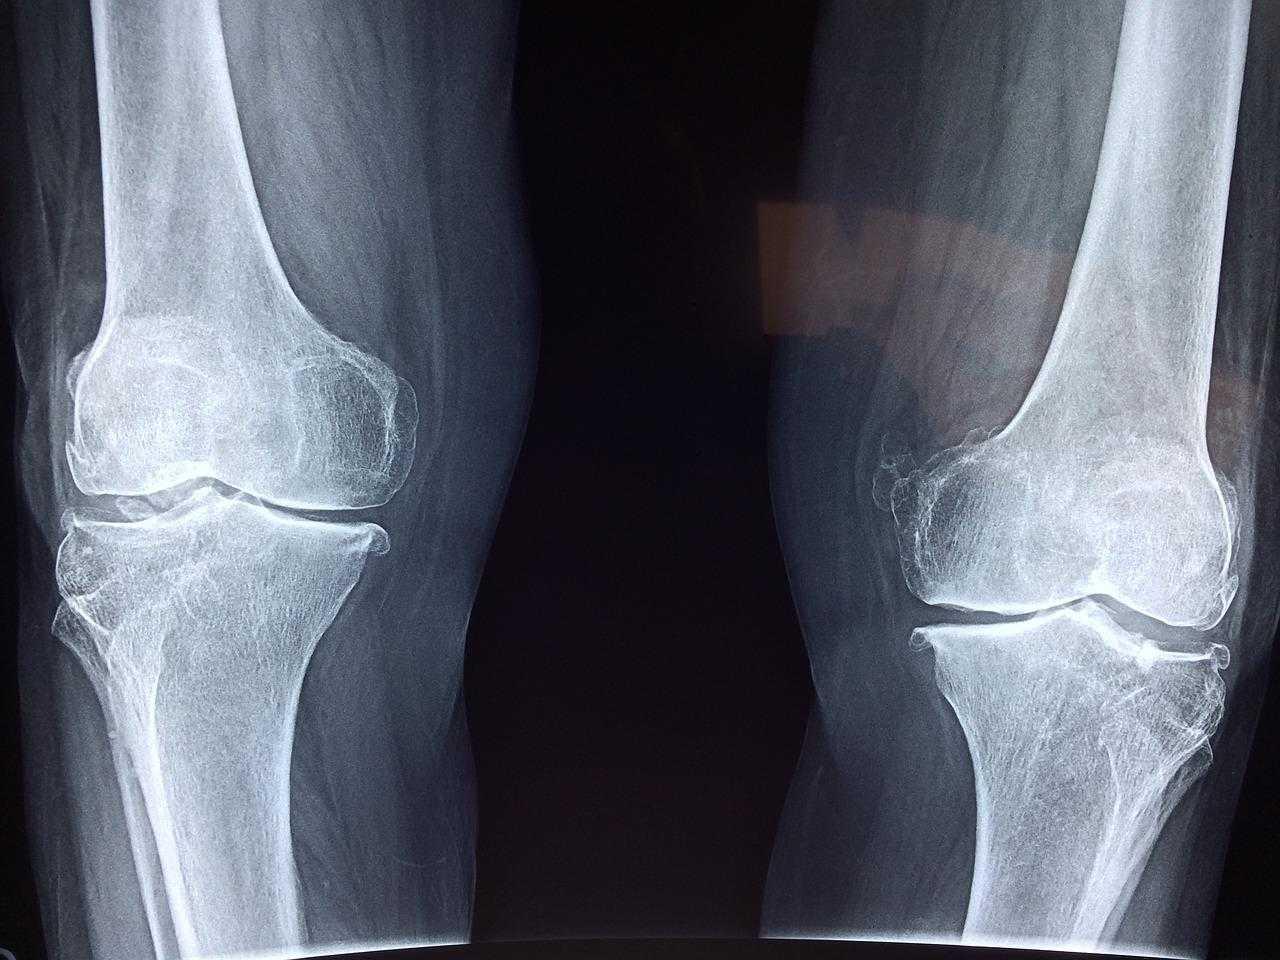

يُعد تمزق الغضروف الهلالي من أكثر إصابات الركبة شيوعًا، خاصة بين الرياضيين أو الأشخاص الذين يبذلون مجهودًا بدنيًا كبيرًا.

⚠️ ما هو تمزق الغضروف الهلالي؟

الغضروف الهلالي هو جزء مهم داخل مفصل الركبة يعمل على:

وعند تعرضه للتمزق، يشعر المريض بألم وصعوبة في الحركة.